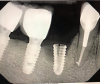

Implants with internal hex connections are more prone to failure at the connection than those with external hex connections.28 This is related to the thickness of the metal at the thinnest point between the internal surface of the interface and the external surface at the crestal area of the implant. When overloaded, implants with an internal hex connection may present with fractures at the points of the hex.29 These points are where the metal is the thinnest at the crestal portion of the implant and where stress is concentrated during overloading. This is less problematic in wider diameter implants because the metal is thicker in this area of the implant; however, in standard or narrow diameter implants, fracture may result, causing catastrophic failure of the implant (Figure 1). This may also occur in other internal implant connection types, such as trilobe connections, especially when the crestal thickness of the implant is minimal, leading to fracture of the coronal aspect of the implant (Figure 2). Implants with conical connections are not immune to potential fracture in this area, and the thin walls of some standard or narrow diameter models may split even without the isolated stress points observed in internal hex-, trilobe-, and octagon-type connections (Figure 3).30 Sometimes, fractures of implants at the coronal aspect are not clinically visible but, instead, are identified radiographically either after a patient complaint of pain in the area, due to the presence of soft-tissue inflammation, or during a routine examination with no patient complaint (Figure 4).

(4.) A failed implant that underwent mechanical overloading leading to fracture of the coronal portion adjacent to the implant-abutment connection.

Figure 4